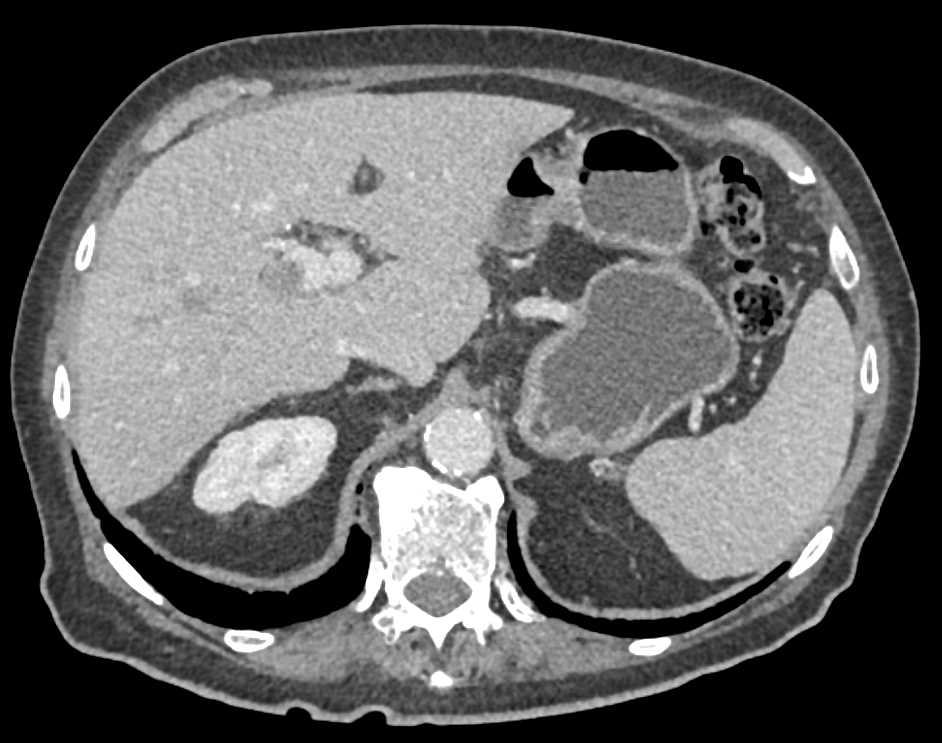

Vascular Collaterals due to Portal Vein Involvement